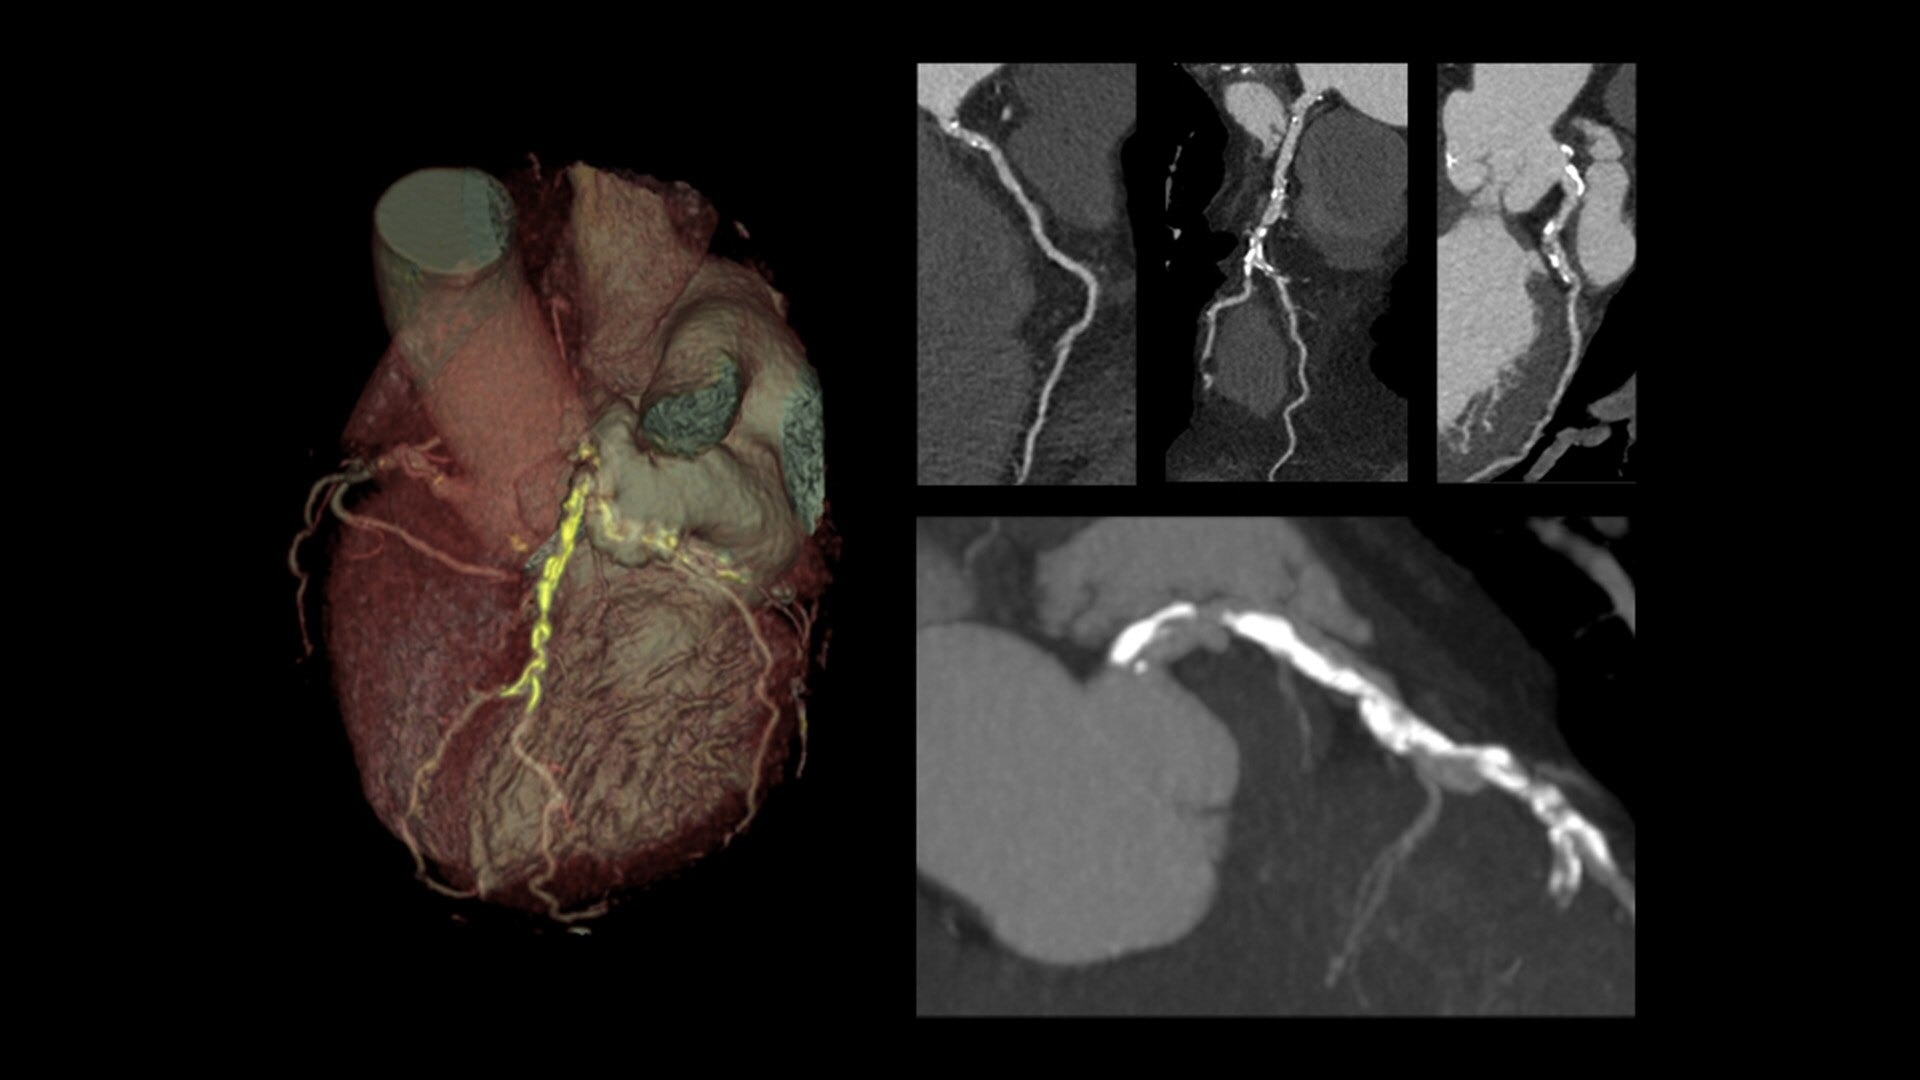

The ECG-less CT (a cardiac CT scan without an ECG trace) is an industry-first

Increases Cardiac CT access

Address cardiac exams where patient access and speed need to be prioritized

Simplified workflow

Useful in exams where excluding ECG traces would streamline patient preparation